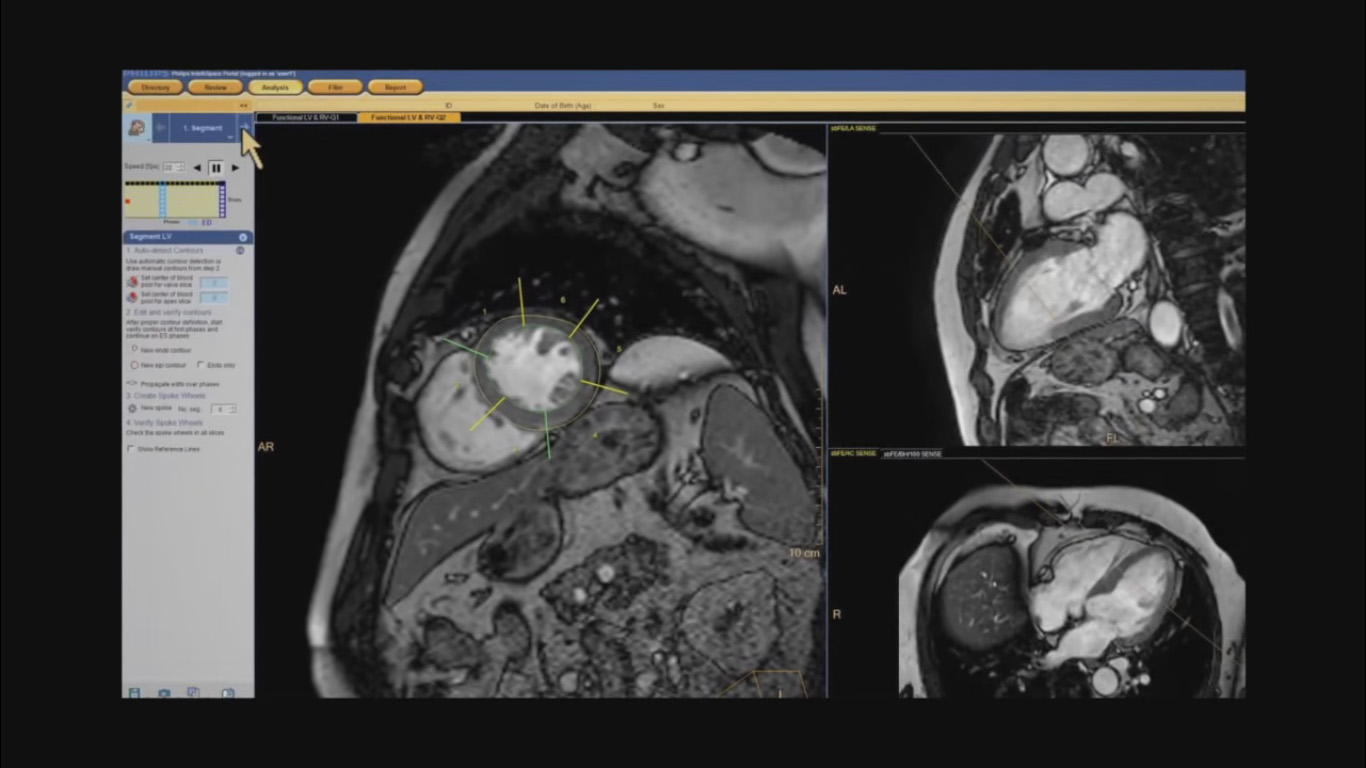

“By using Philips’ advanced imaging techniques like 3D, MIP, and MPR, we can easily bring up images and manipulate them to fine-tune our diagnoses. We get a better idea of the extent of the disease and can make better recommendations to the clinician about what’s going on.” Dr. D’Arcy Little

MD, CCFP, FRCP, Radiologist, Orillia Soldiers’ Memorial Hospital, Orillia, Ontario